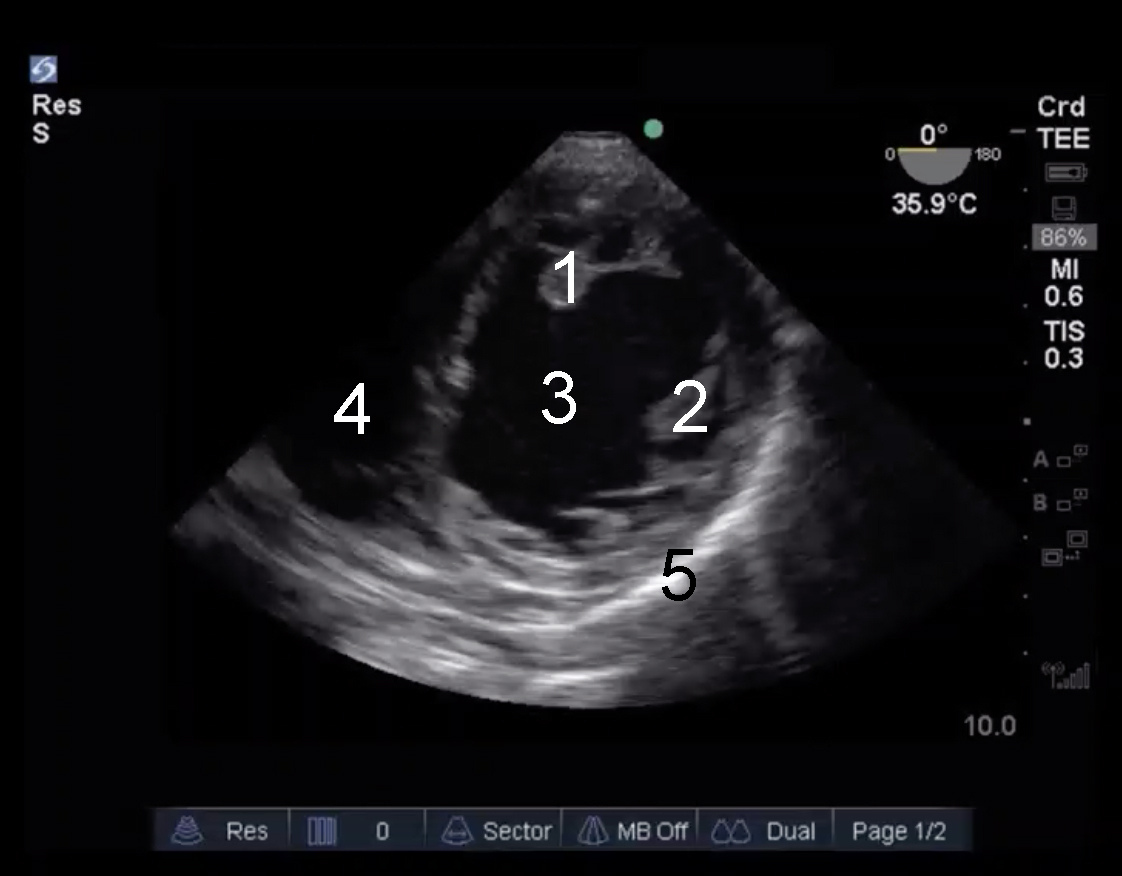

Cardiac 2 TEE Trans Gastric Image

1. Posteromedial Papillary Muscle

2. Anterolateral Muscle

3. Left Ventricle (LV)

4. Right Ventricle (RV)

5. Pericardium